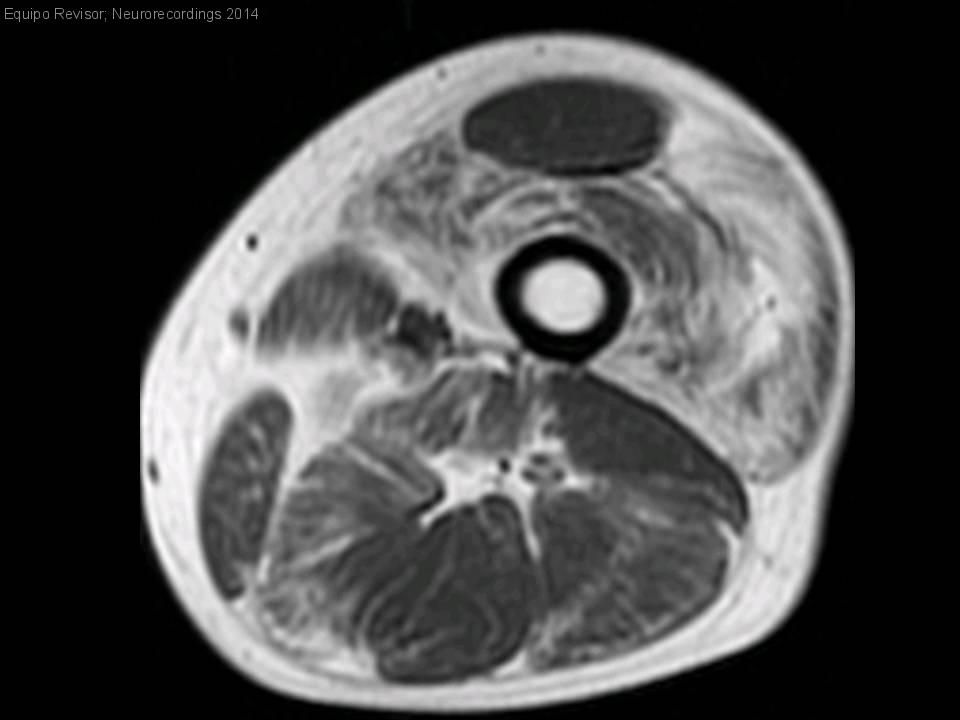

Hombre | 60 años

Diagnóstico final: Miopatía central core por mutación en RyR1

Neurología: Neuromuscular / ataxias

Etiología: Genético / idiopático